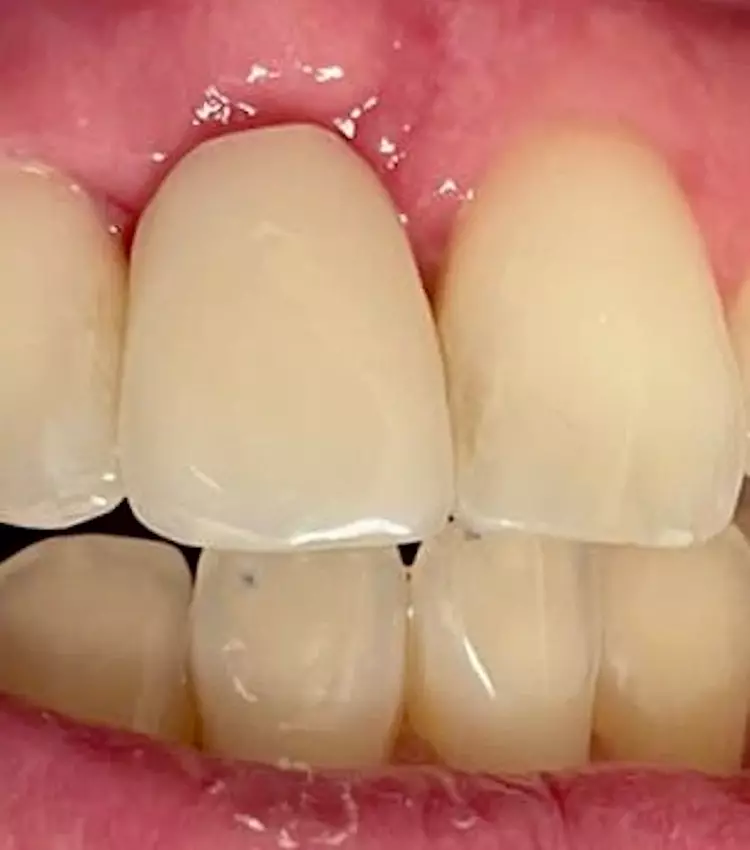

Durch den intraoperativ wiederhergestellten Alveolarkamm und die damit gestützte keratinisierte Gingiva konnte ein natürliches Emergenzprofil wiederhergestellt werden, unter Erhaltung der Interdentalpapillen. Dies zeigte sich auch bei der radiologischen und klinischen Kontrolluntersuchung nach Eingliederung des Zahnersatzes (Abb. 15 und 16).

Zahnklinik Bochum